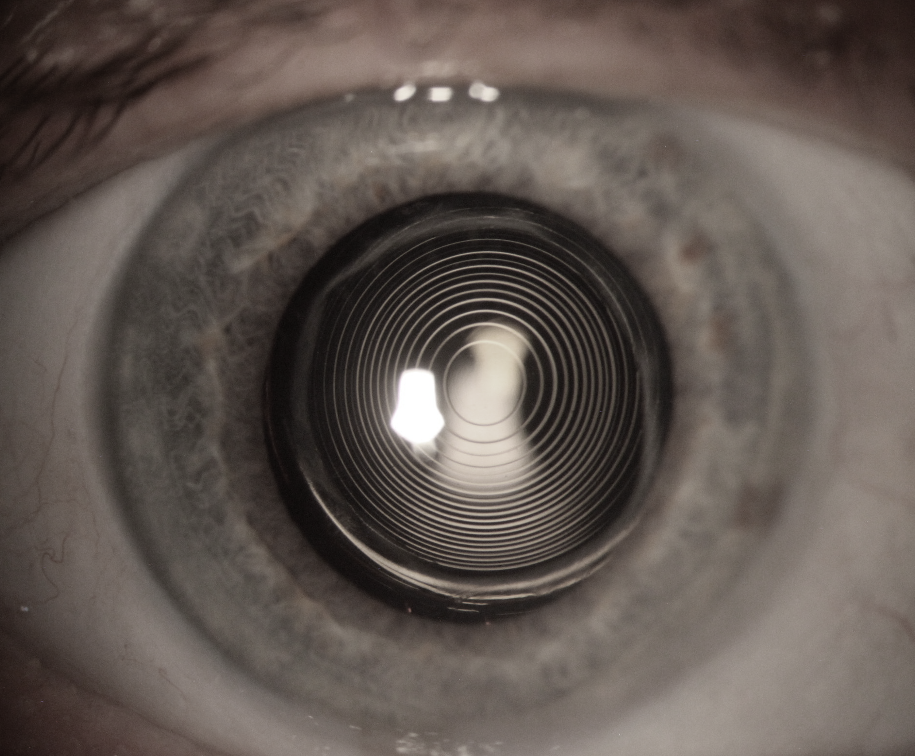

Corrigez votre vision avec les dernières techniques de pointe et retrouvez une vision claire et nette sans lunettes ni lentilles. Grâce aux techniques LASIK, PKR ou SMILE ou encore aux implants oculaires, tous les défauts visuels peuvent maintenant être soignés.

Retrouvez une vision nette et améliorez votre qualité de vie grâce à une expertise spécialisée en chirurgies de la cataracte, de la rétine (décollements de rétine, membrane épirétinienne, trou maculaire), du glaucome et greffes de cornée lamellaire ou totale.